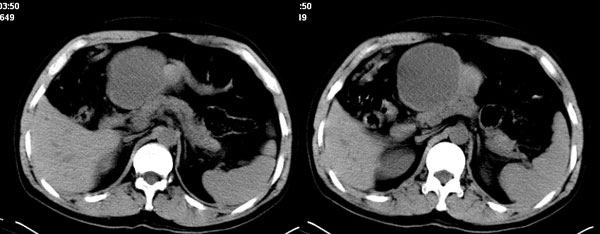

李**,男,46岁,便血1天入院,慢性贫血貌,腹平、软,剑突下压痛,肠鸣音稍活跃,hb大于1g/l,胃镜:慢性浅表性胃炎,b超:1肝内多发性占位 2腹腔内囊性肿块 ,肝内圆形影平扫ct值42.9,动脉期48.6,静脉期58.2,延迟期62.2

影像学表现:1 腹腔前中部、胰腺前方囊实性病灶(个人认为确定有否实性成分存在这是关键,涉及到鉴别诊断,如果是口服阳性造影剂则可明确左侧是不是小肠了),囊性部分囊壁不均,实性部分有强化,与小肠关系较密切,局部小肠受推移;与胰头、胃后壁均有脂肪间隙存在;2 胰腺无异常改变,胰周无渗出;3肝后段包膜下2个小圆形低密度灶,从图像和楼主提供的ct值来看有轻度强化,灶周无片状强化,不似单纯囊肿及肝癌、炎性病变表现;4 腹膜后及腹腔内无淋巴结肿大。

胰腺边界清晰,胰周筋膜不厚,胰周脂肪密度无明显增高;其前方囊实性病灶,边界清晰,增强后实性部分轻度强化;肝内多发边界清晰低密度影,增强后无明显强化(平扫ct值42.9,动脉期48.6,静脉期58.2,延迟期62.2)。